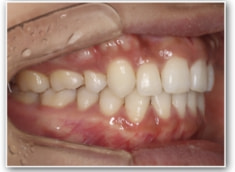

治療後